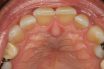

Nasopalatine duct cyst

A developmental, nonodontogenic cyst originating from embryonic remnants within the nasopalatine duct. Also known as an incisive canal cyst.